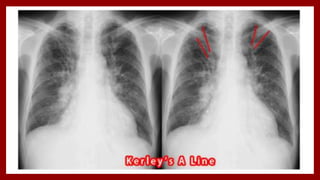

Chest X-Ray

• Cardiomegaly

• Cephalization of blood flow

• Kerley’s A lines [1- to 2-cm lines of

interstitial edema out from the hilum]

• Kerley’s B lines [short, thin, flattened

streaks of interstitial edema outlining

the subsegmental lymphatics that

extend from the pleural surface]

Chest X-Ray • Cardiomegaly •Cephalization of blood flow • Kerley’s A lines [1- to 2-cm lines of interstitial edema out from the hilum] • Kerley’s B lines [short, thin, flattened streaks of interstitial edema outlining the subsegmental lymphatics that extend from the pleural surface]